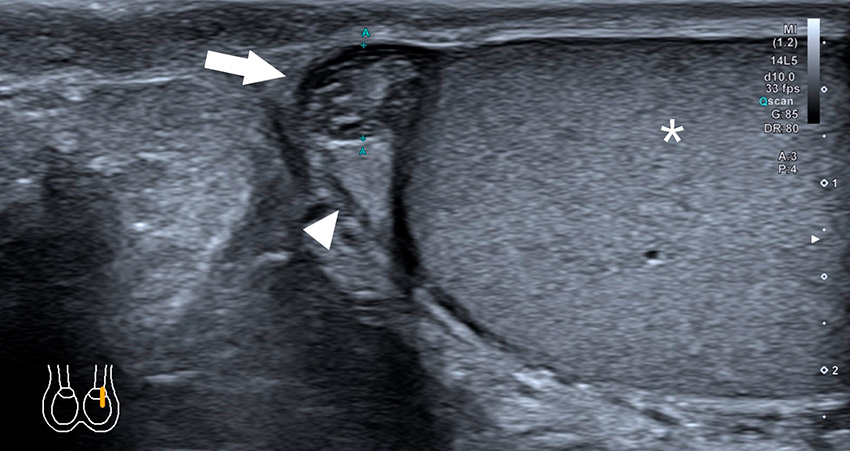

Torsion av intraskrotalt bihang. Invid caput epididymis (pilspets) finns en rund, 5 mm stor inhomogen struktur (pil) som utgörs av torkverad appendix testis. Testikelparenkymet (asterisk) är normalt. Ibland kan en sekundär hyperemi av epididymis ses.